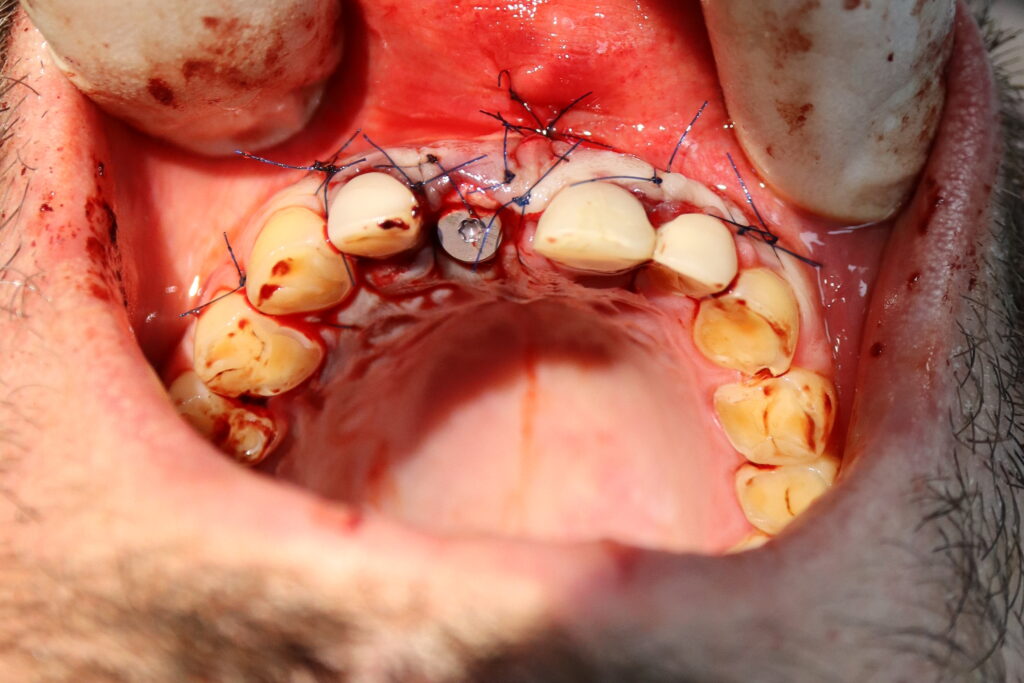

Процесс работы

Что было сделано:

Хирургом-имплантологом были проведены следующие манипуляции: удаление зуба 1.1, удаление кисты, аугментация твердых и мягких тканей в области 1.1

с применением свободного соединительнотканного трансплантата из слизистой оболочки бугра верхней челюсти, пластика уздечки верхней губы.

Установлен имплантат Straumann BLT и формирователь десны.

В этот же визит терапевтом был изготовлен адгезивный протез для устранения эстетического дефекта до момента остеоинтеграции имплантата.

Постоянная коронка будет установлена спустя 3 месяца.

удаление зуба

Это фото может содержать тяжелый для восприятия контент